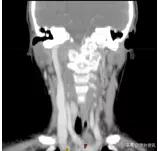

这可把珊珊爸爸妈妈急坏了,辗转多家大医院,颈部核磁共振检查发现颈椎、枕骨骨质广泛破坏、周边软组织形成(图一),后经病理检查确诊为朗格汉斯细胞增多症,是一种良性病!

图一 治疗前CT

但是随后医生的交待又让他们凉了半截,因骨质破坏范围较大,且位置特殊,无法手术治疗,如果病情进一步发展,随时可能出现颈椎骨折危及生命。